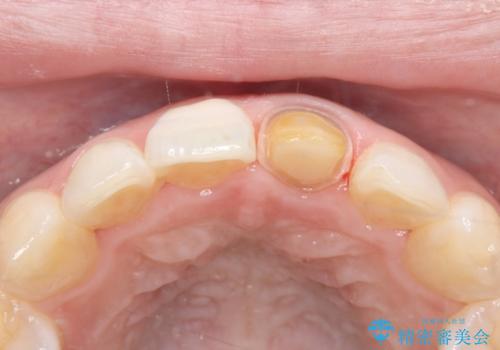

- 「以前、他院で神経を取った前歯がだんだん黒ずんできた」という見た目の改善を主訴にご来院されました。 診査の結果、神経を取り除いた後の歯(失活歯)特有の変色が起きており、さらに根の先端にわずかな影が見られたため、内部で感染が起きている可能性がありました。

そこで、まずは土台を外して根の内部をきれいにする再根管治療を行い、基礎をやり直した上で、透明感の高いオールセラミッククラウンで被せ直す治療計画を立案。単に白くするだけでなく、再発を防ぎ、長期的に美しい状態を保つことを目指しました。

精密な再根管治療: 古い充填材を除去し、歯科用顕微鏡を用いて根管内を徹底的に清掃・殺菌しました。根の先まで確実に薬剤を詰め直すことで、将来的な根尖病変(根の先の膿)のリスクを最小限に抑えました。